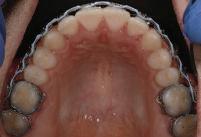

Dental Tribune Bulgarian Edition / октомври 2022 г.16 клиничен случай с алайнери Г орният латерален ре зец е вторият найчесто вродено липсващ зъб.1,2 Поради разполо жението му във видимата зона на усмивката лечение то на подобни случаи нала га мултидисциплинарен под ход, целящ отличен функцио нален и естетичен резултат. Налице са няколко лечебни мо далности, свързани с различ но разпределение на място то: първият вариант е орто донтско отваряне на място и възстановяване на липсва щия зъб с конструкция, под държана от съседните зъби3 или от имплант4, докато при втория подход разстоянията се затварят и премоларът заема мястото на канина.5 Изборът на лечебен подход трябва да бъде направен съв местно от зъболекар и паци ент въз основа на очакванията на последния и предвиди мостта на лечението. Множе ство фактори влияят върху това решение, като напри мер типа малоклузия, размера, формата и цвета на кучеш ките зъби6, оклузалните вза имоотношения (овърджет и овърбайт), лицевия профил, дължината на зъбната дъга и несъответствията в разме ра на зъбите.7 В настоящата публикация се разглежда случаят на жена в зряла възраст с вродена лип са на горен ляв латерален резец. Бяха приложени про зрачни алайнери за отваряне на място за единичен им плант и бяха постигна ти функционална оклузия и отлична естетика. ПРЕДСТАВЯНЕ НА СЛУЧАЯ Диагноза Пациентката бе на 32 годи ни, когато лечението започна, и първоначалното ѝ състоя ние бе следното (фиг. 1–3): липсващ горен ляв латерален резец; клас II, подклас I малоклузия; отклонение на горната сре динна линия вляво; Доклад на клиничен случай ЛЕЧЕНИЕ С АЛАЙНЕРИ НА ПАЦИЕНТ С АГЕНЕЗИЯ НА ЛАТЕРАЛЕН РЕЗЕЦ Д-р Iro Eleftheriadi и д-р Christodoulos Laspos, Гърция и Кипър Фиг. 1a–h Предоперативни лицеви и интраорални снимки. Фиг. 2a–e Дигитални модели преди началото на лечението. Фиг. 3 Панорамна снимка преди лечението. Фиг. 1a Фиг. 1d Фиг. 1f Фиг. 2a Фиг. 2d Фиг. 2b Фиг. 2e Фиг. 3 Фиг. 2c Фиг. 1b Фиг. 1e Фиг. 1g Фиг. 1h Фиг. 1c

Dental Tribune Bulgarian Edition / октомври 2022 г. 17клиничен случай с алайнери леко струпване в долната че люст; несъответствие по Болтън (мандибуларен излишък от 3.06 мм във фронталната зона и общо 1.47 мм); издължено лице с лицева аси метрия; конвексен профил с ретруди рана долна челюст и проми нентен нос. На мястото на зъб #46 бе на лице имплант, а зъби #16 и 26 са ендодонтски лекувани. Тези зъби бяха асимптоматич ни, затова бе взето решение да се прави релечение само при нужда. Мъдреците липсваха. Анализът на телерентгеногра фията (фиг. 4) показа ретрог натна мандибула (SNB: 74.2°) и нормална инклинация на резците както в

Цели на лечението и лечебен план Целите на лечението бяха следните: нивелиране и подреждане на зъбите и в двете зъбни дъги; отваряне на пространство за липсващия латерален резец; коригиране на отношенията при канините и моларите до клас I; и корекция на отклонението на срединната линия. Лечебният план включваше: корекция на отношенията при кучешките зъби и мола рите до клас I с дистализира не на максилата; отваряне на пространство в областта на #22 за поставя не на единичен имплант; корекция на срединната ли ния; и създаване на място за раз ширяване на зъб #12 и апрок симална редукция в долната челюст с цел подобряване на несъответствието по Болтън и осигуряване на подобра оклузия. Изпълнение на лечебния план Този случай бе изпълнен със системата за алайнери Invisalign (Align Technology). Одобреният първоначален лечебен план предвиждаше 49 алайне ра с дистализиране на задни те горни зъби до клас I (прибли зително с около 3.5 мм; фиг. 5). За бъдещия имплант в областта на липсващия латерал бе планирано пространство от 6.5 мм, докато във фронталния сегмент на долната челюст бе предвидена апроксимална редук ция. В дясната страна бутон за ластици клас II бе поставен на зъб #47 вместо на зъб #46, за да не се увреди короната на импланта. Понеже пациентката жи вееше в чужбина,

следните казуси: недобра оклу зия в дисталните зони по вре ме на дистализирането на гор ната челюст и накланяне на зъб #21 (фиг. 7). Последното се дължи на липсата на компози тен атачмънт на този зъб, каквото не бе зададено в пър Фиг. 4 Телерентгенография и цефалометричен анализ преди началото на лечението. Фиг. 5a–e Одобреният първоначален лечебен план. Фиг. 6a–h Снимки по време на лечението, показващи нуждата от внасяне на някои корекции. Фиг. 4 Фиг. 5a Фиг. 5d Фиг. 6a Фиг. 6d Фиг. 6f Фиг. 6b Фиг. 6e Фиг. 6g Фиг. 6h Фиг. 6c Фиг. 5e Фиг. 5b Фиг. 5c

Dental Tribune Bulgarian Edition / октомври 2022 г.18 воначалния план. Тези пробле ми бяха адресирани чрез допъл нителна поръчка на алайнери с торк контрол и зададено екст рудиране на задните зъби с цел установяване на добри оклузал ни контакти в дисталните об ласти, като бяха предвидени и оптимизирани атачмънти с контрол над корените за корекция на ангулацията на макси ларните резци (фиг. 8). Резултати от лечението Панорамната рентгено графия след ортодонтското лечение показа благоприятна паралелна позиция на съседни те зъби, подходяща за поставя не на имплант в областта на #22, както и конвергенция на ко рените на зъби #44 и 45 (фиг. 9), но преценихме, че няма да от деляме допълнително лечебно време за коригирането ѝ поради факта, че пациентката бе мно го доволна от постигнатия до момента резултат. След при ключване на лечението бяха постигнати отлични взаимо отношения клас I при мола рите и канините, а срединни

съвпадаха. Върху им

(LFH: 56.5 mm) и размерите на меките тъка ни останаха непроменени. На клонът на горните резци бе за пазен (Ui–FH: 115.8°), а долните резци бяха леко наклонени ве стибуларно (Li–APog: 30°; фиг. 16). ДИСКУСИЯ Липсата на зародиш на по стоянен горен латерален резец е налице при 3.5–6.5% от евро пеидната раса, като при жени е по-честа, отколкото при мъ жете в съотношение 3:2.8–10 Възможни са няколко лечебни подхода, включително замя ната му с преоформен канин, отваряне на място чрез орто донтско лечение и протетич но възстановяване, както и ав тотрансплантация. Устано вено е, че изборът за затваря не на място или за отваряне то му все още подлежи на дис кусия сред ортодонти и проте зисти.11,12 Според литературните дан ни затварянето на простран ството и замяната на липсва щия латерал с канин се предпо чита в случаи на едностранна липса на зародиш, балансиран профил, кучешки зъби и премола ри със сходна форма и цвят, дву челюстна протрузия или клас II малоклузия.13–15 Отваряне на пространство по-често се изби ра при клас I, наличие на диасте ми и треми в горната зъбна дъга или голяма разлика в размерите на канини и премолари.16 Скорошно проучване е уста новило, че изборът на лечение при конгенитално липсващ ла терал е пряко свързан със след ните фактори17: възрастта на пациента при започване на лечението; индивидуалните особености при всеки конкретен случай; и сътрудничеството между специалистите в лекуващия екип. Макар да има проучвания, фа воритизиращи леченията със затваряне на място11,18, всеки случай трябва да бъде оценяван индивидуално. В презентирания в тази статия случай бе взето решение за отваряне на мяс то и протетично възстановя ване, понеже целта бе да се по стигнат клас I отношения при канините и моларите, както и по-широка усмивка. За да се из бегнат компромиси, след лече нието бе постигнат клас I при моларите и кучешките зъби, несъответствието по Болтън бе подобрено и срединната ли ния бе коригирана. Други изслед вания демонстрират отлични естетични и функционални ре зултати при лечение с отваря не на място и протетична ре хабилитация.19 И двете лечеб ни модалности са подходящи за третиране на вродена лип са на зародиш на латерал и да ват сходни функционални и па родонтални резултати20, като при едно проучване

ти и клас II ластици е устано вено, че осигурява достатъч на дистализация без промяна на лицевата височина.23 Както се видя от цефалометричния анализ, точно това бе постиг нато и в представения случай като се има предвид, че лице вата височина остана същата като първоначалната. Предвид леката тенденция към дистал Фиг. 8a–e Поръчаните допълнителни алайнери. Фиг. 9 Панорамна рентгенография след края на лечението. Фиг. 10a–c Странични (а и с) и фронтална интраорални снимки след края на ортодонтското лечение и поставянето на импланта (b). Зъб #12 все още не беше протезиран. Фиг. 11а и b Оклузални снимки след ортодонтското лечение. Фиг. 7a Фиг. 8a Фиг. 7d Фиг. 8d Фиг. 9 Фиг. 10a Фиг. 10b Фиг. 10c Фиг. 11bФиг. 11a Фиг. 7b Фиг. 8b Фиг. 7e Фиг. 8e Фиг. 7c Фиг. 8c Фиг. 7a–e Интраоралната ситуация по време на лечението. клиничен случай с алайнери

Dental Tribune Bulgarian Edition / октомври 2022 г. 19 на отворена захапка е устано вено, че финалното адаптиране и подобряване на оклузалните контакти се установяват след повече от три месеца след лече нието.24 Следователно подобря ване на ситуацията и плътни оклузални контакти се очак ват след края на лечението. Що се отнася до избора за замест ване на липсващия латерален резец с единичен имплант и протезирането му, установе но е, че това е най-често при лаганата лечебна алтернати ва.25 Съседните зъби остават интактни и следователно най голямото предимство на този подход е съхраняването на здра ви зъбни структури. Изборът ни на лечебен план бе базиран на детайлна мул тидисциплинарна диагноза и планиране, а те категорично са ключови за постигане на оп тимални индивидуални резул тати при пациенти

но

между членовете на екипа и пациента. ЗАКЛЮЧЕНИЕ Случаите на липсващи лате рални резци трябва да бъдат третирани от перспектива та на интердисциплинарна ди агностика и лечение. Употреба та на софтуера ClinCheck има доказани предимства за плани ране, комуникация между кли ницистите и пациента и фи нализиране на лечебния план, като се адресират всички же лания и притеснения на паци ента. Настоящият доклад на клиничен случай доказва, че с помощта на съвременните ме тоди един успешен екип от спе циалисти (ортодонт, консерва тивен зъболекар и хирург) може да се стреми към отлични ре зултати и да постига есте тични и функционални усмив ки без компромиси. Ред. бел.: Статията Treatment of a patient with a congenitally missing lateral incisor using aligners: A case report е пуб ликувана за първи път в сп. aligners–international magazine of aligner orthodontics, бр. 1, издание 1/2022. Библиографията е налична при издателя. За авторите: Д-р Iro Eleftheriadi завършва дентална медицина в Атинския университет, а магистратурата си по медицинска статистика – през 2014 г. в Публичния университет в Атина, Гърция. Специализира ортодонтия и завършва през 2017 г. в Университета в Тел Авив, Израел. Предстои ѝ да защити докторан тура във Факултета по дентална медицина към Университета в Атина, Гърция. Д-р Christodoulos Laspos завършва дентална медицина през 1995 г. в Атинския университет, Гърция, а магистратурата си завършва през 1999 г. във Фа култета по дентална медицина към Университета в Тенеси, Мемфис, САЩ. Печели стипендия и специализира лечение на пациенти с лицево-челюстни малформации в Университета в Тексас, Далас, САЩ, и е сертифициран специалист от Европейския борд на ортодонтите. Той е докторант в Универ ситета в Берн, Швейцария. От 2000 г. д-р Laspos практикува в частната си ортодонтска практика в Лимасол, Кипър. Той е основател и директор на MEDICLEFT, Кипърски център за цепки и лицево-челюстни аномалии, както и директор на фондацията Synergy, която осигурява следдипломно обучение на лекари по дентална медицина. Научен съ трудник е във Факултета по дентална медицина към Европейския университет в Кипър. Д-р Laspos изнася лекции по цял свят по теми като лицево-челюстни мал формации, ортогнатна хирургия, мултидисциплинарен подход и нови технологии в ортодонтията. Той е активен член на Европейското общество на Енгел и прези дент на Европейското ортодонтско общество. Фиг. 12а–c Финални странични (а и c) и фронтална интраорални снимки (b). Фиг. 13а и b Финални оклузални снимки. Фиг. 14 Финална снимка на усмивката отблизо. Фиг. 15 Финална екстраорална снимка на усмивката. Фиг. 16 Финална телерентгенография и цефалометричен анализ. Фиг. 12a Фиг. 13a Фиг. 14 Фиг. 15 Фиг. 16 Фиг. 13b Фиг. 12b Фиг. 12c клиничен случай с алайнери